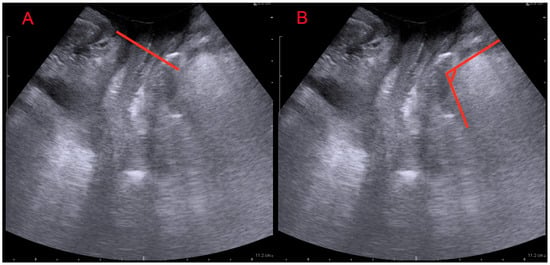

| ARA (°) | 84.8 ± 7.7 | 111.3 ± 5.9 | <0.001 |

| LAMD (mm) | 39.4 ± 2.9 | 50.3 ± 3.1 | <0.001 |